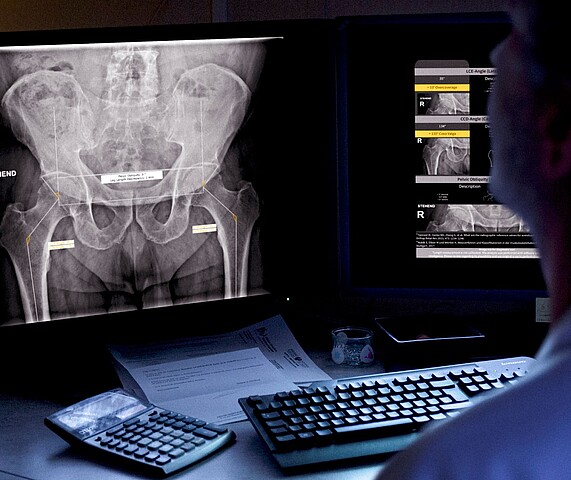

ImageBiopsy Lab: Wiener KI verändert die Radiologie

Wie ein Wiener MedTech-Unternehmen Routinearbeit in der muskuloskelettalen Diagnostik automatisiert – und damit Qualität, Tempo und Vergleichbarkeit von Befunden erhöht.